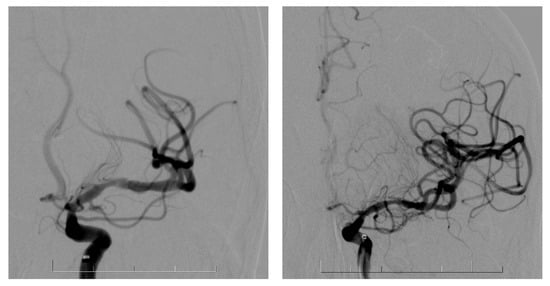

7.2. Endovascular Treatment of AIS

Endovascular treatment of anterior circulation AIS was performed in routine practice with a maximalist approach to achieve the best possible first-pass effect. We routinely proceeded with stenting after at least two good but unproductive passes of a mechanical thrombectomy or if vessel dissection was obvious on DSA or FD-CT (Figure 1).

Figure 1. DSA with MCA dissection before and after the stent placement.